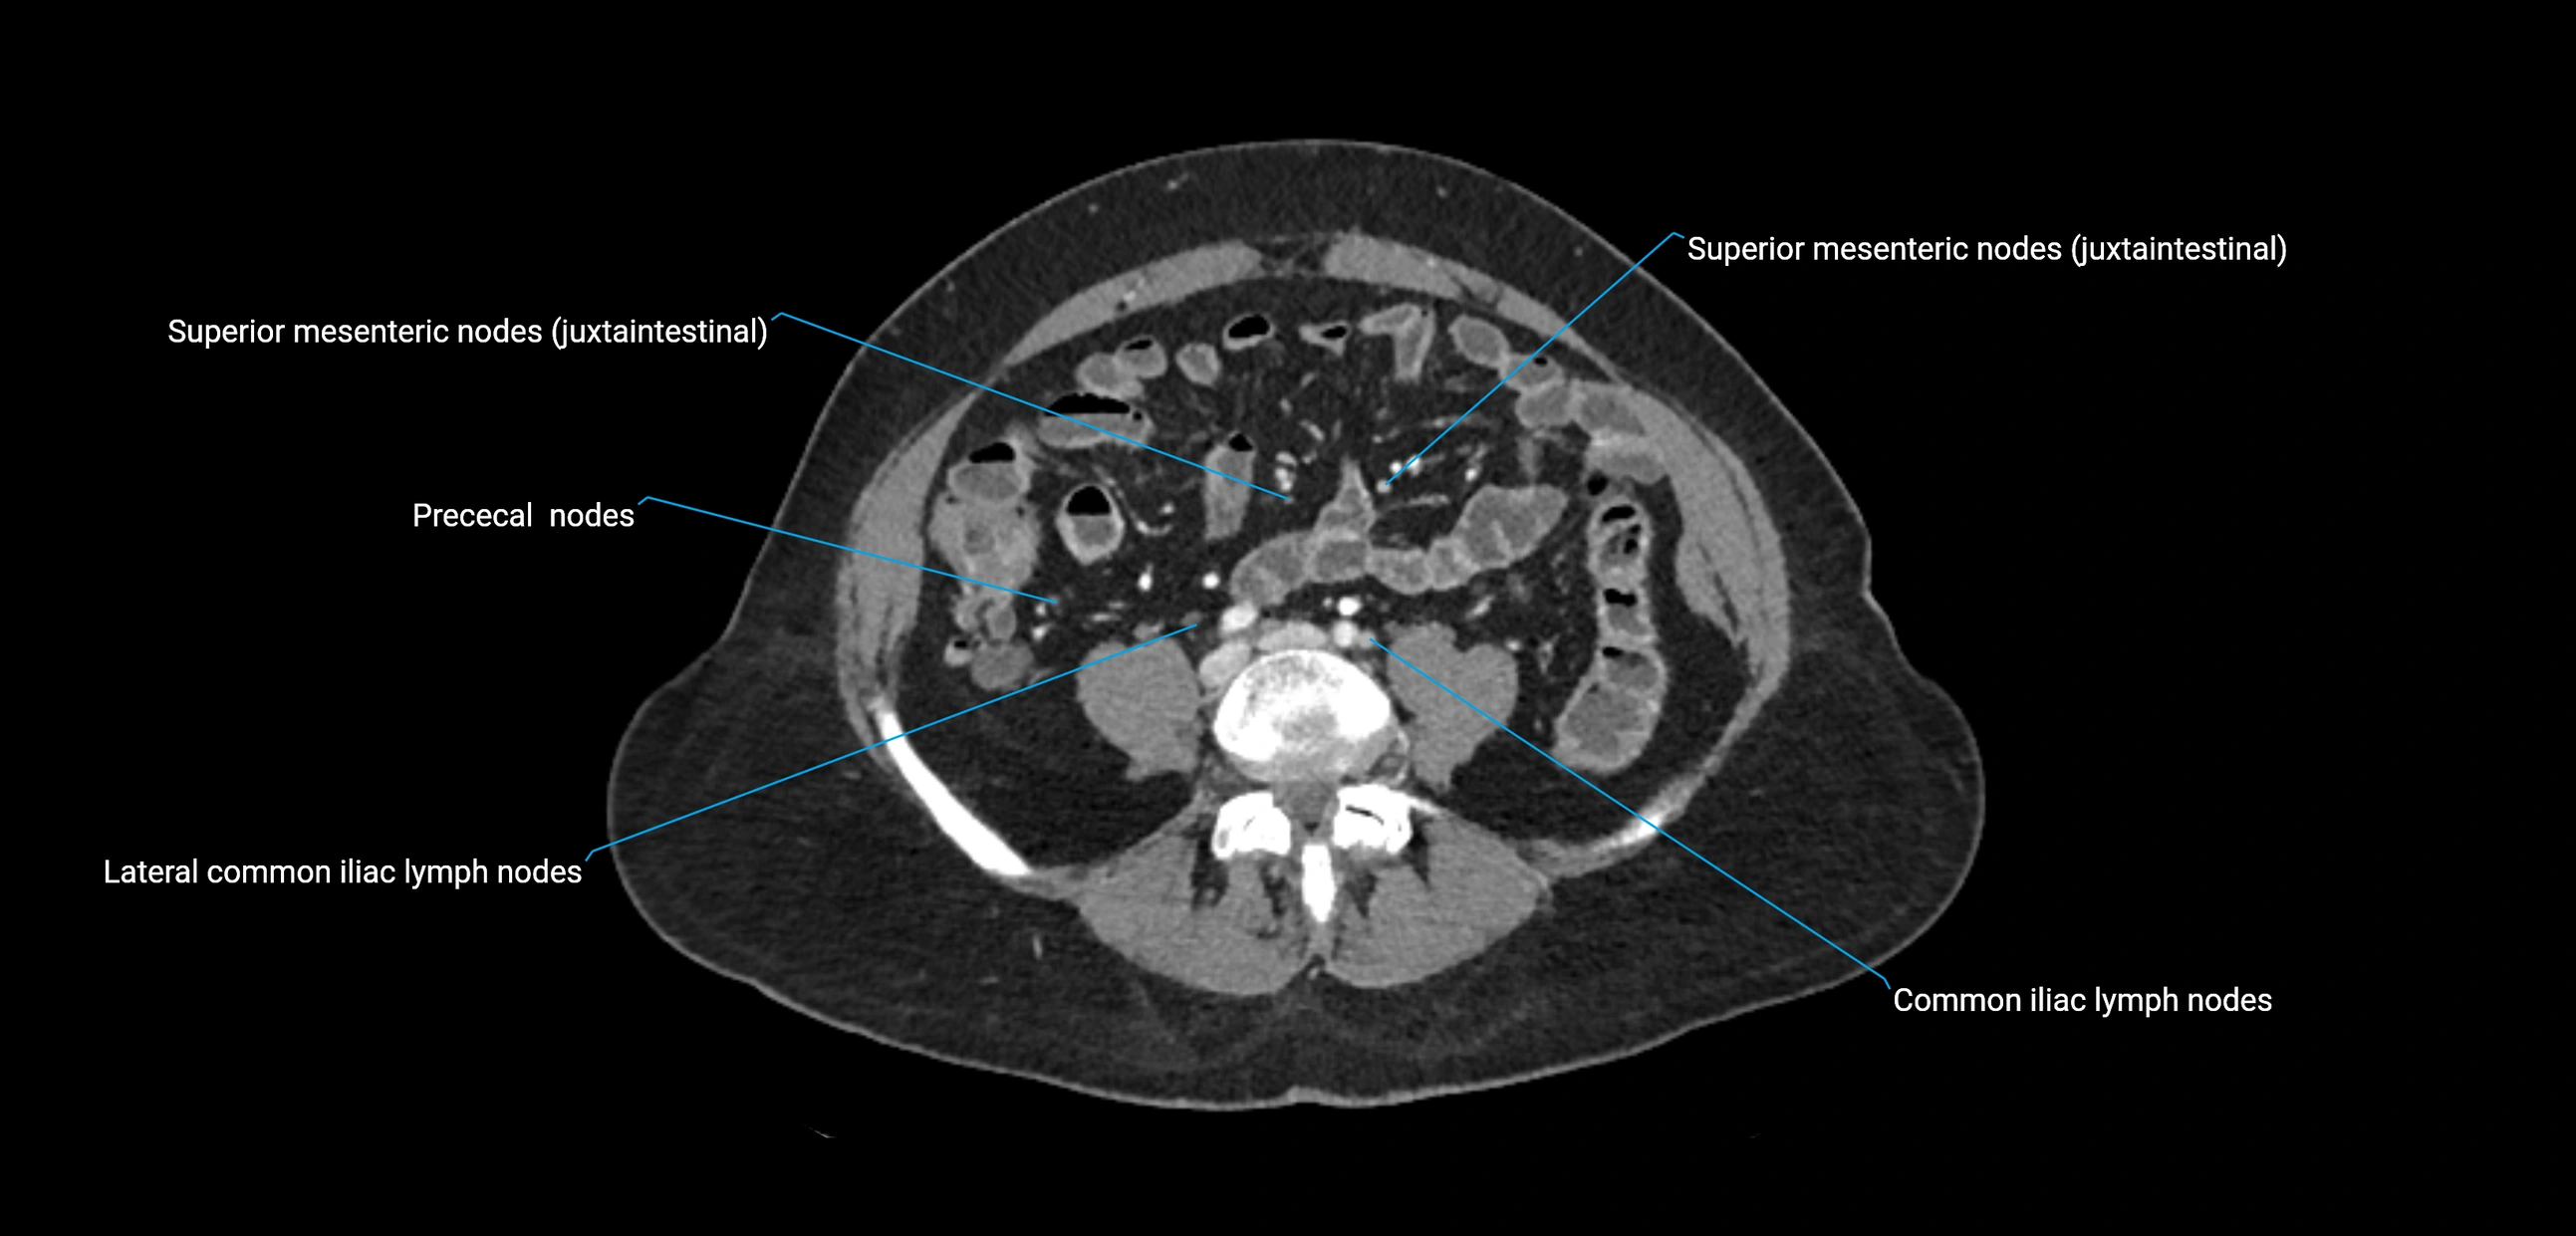

CT Appearance

CT Pre-Contrast:

• Nodes appear as soft-tissue density nodules adjacent to the aorta and IVC

• Calcification may be seen in chronic infections (e.g., tuberculosis)

CT Post-Contrast:

• Normal nodes enhance homogeneously

• Malignant nodes may show heterogeneous enhancement, central necrosis, or conglomerate formation

• Size >1 cm short axis is suspicious, though morphology and distribution are equally important